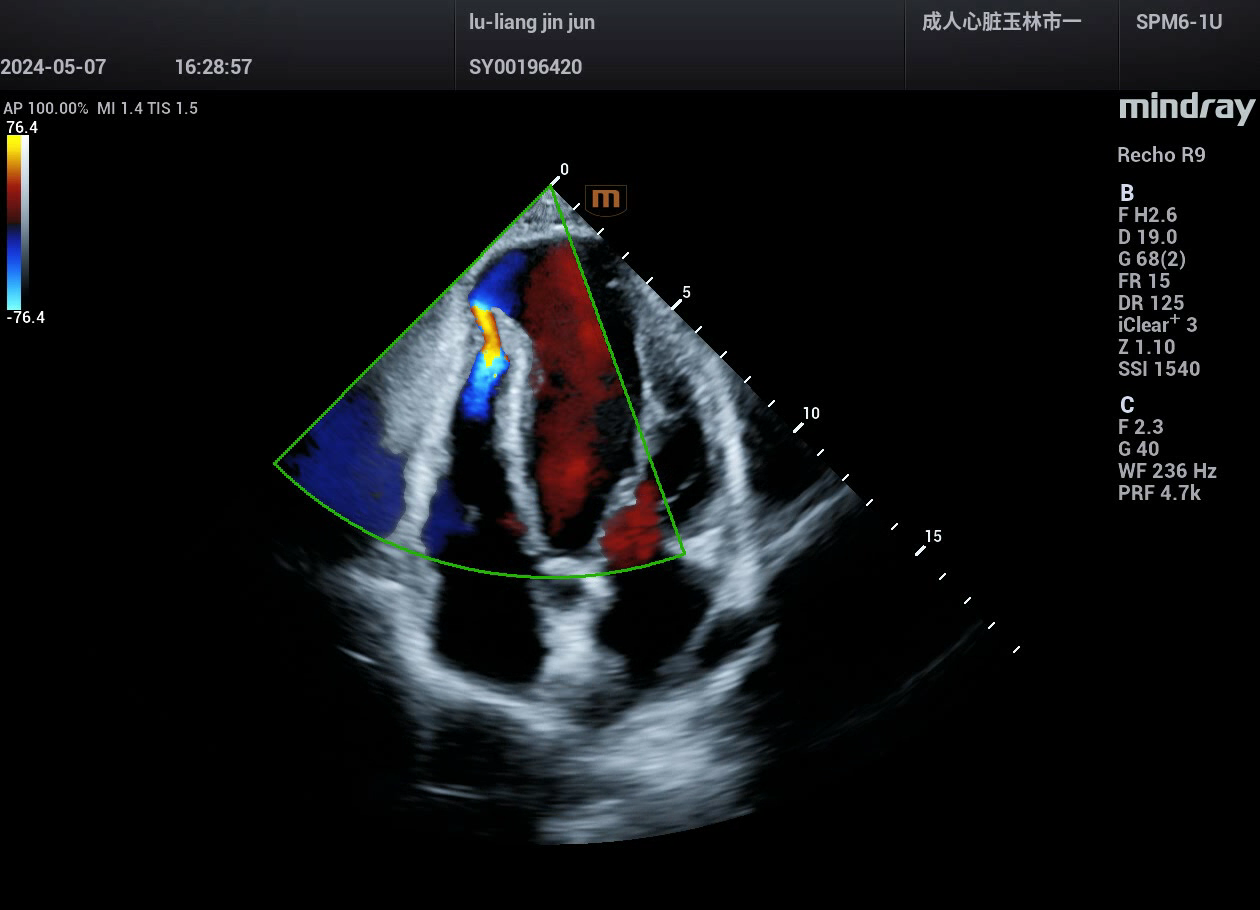

病例,急性心肌梗死,并发室间隔穿孔,迈瑞心脏彩超鲲鹏Recho R9,2024年5月

病例,急性心肌梗死,并发室间隔穿孔。

病例来源,玉林市第一人民医院超声科。

迈瑞心脏彩超鲲鹏Recho R9,2024年5月。

血流显示非常好,灵敏度很高,分辨力很好,流动性连续。